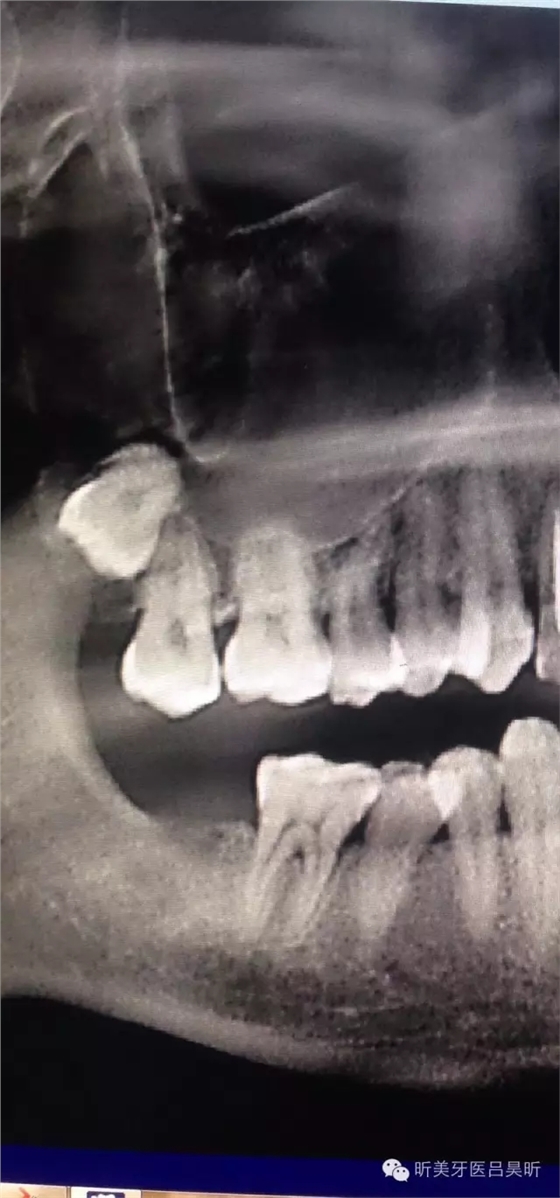

術(shù)前CBCT截圖,垂直骨量似乎感覺良好

可見種植位點舌側(cè)區(qū)凹陷,牙槽骨上部舌傾明顯。